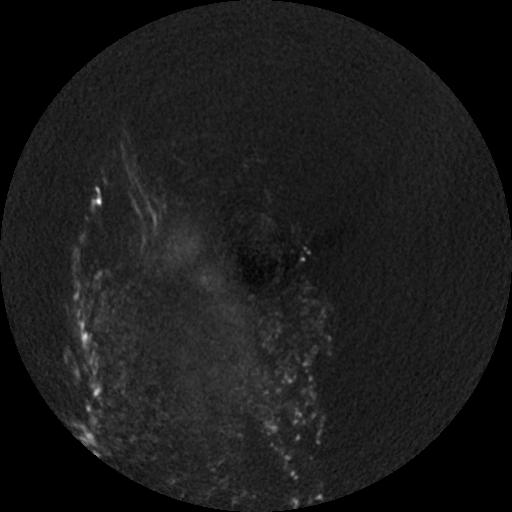

4 CEREBRO,,Vol,0.5,CEREBRO,,